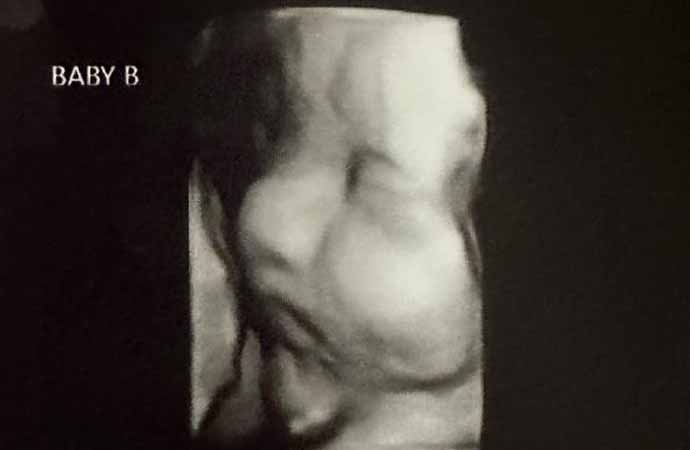

Hatcher'ın doktoru, genç kadının iki rahminde iki ayrı bebeğe aynı anda hamile kalmasının milyonda bir olduğunu söyledi.

Önceki hamileliklerinde sadece tek bir rahminde bebek taşıyan Hatcher, bebeklerin ikiz mi olacağı konusunda henüz bir bilgi veremediklerini söyledi. Durumunu öğrendikten sonra hamileliğini ve sürecini paylaşmak için özel bir sosyal medya hesabı açan Hatcher, bir bağış kampanyası başlattı.